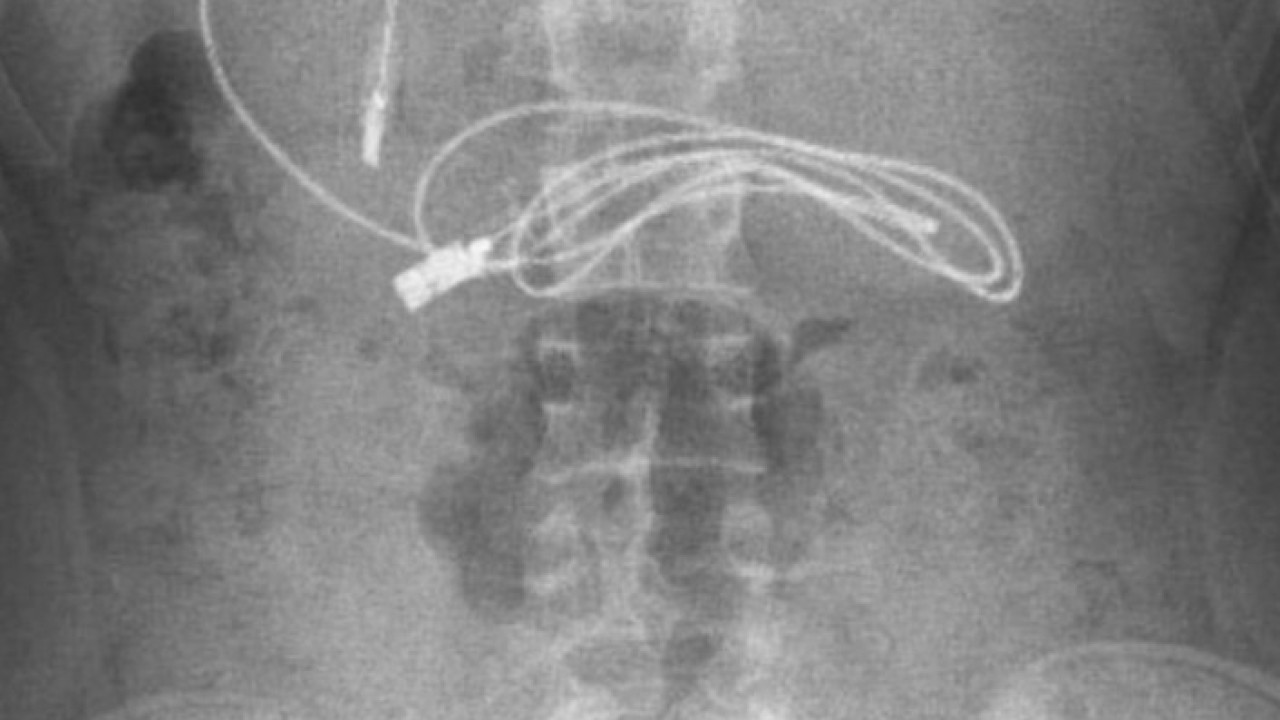

Diyarbakır'da kusma ve bulantı şikayetiyle hastaneye götürülen, çekilen röntgeninde 1 metrelik şarj kablosu ve toka yuttuğu tespit edilen 15 yaşındaki erkek çocuğu, Elazığ'da gerçekleştirilen operasyonla yuttuğu cisimlerden kurtuldu.

Diyarbakır'da kusma ve bulantı şikayetiyle ailesi tarafından hastaneye götürülen erkek çocuğunun çekilen röntgeninde, midesinde şarj kablosu ve toka olduğu tespit edildi. Bunun üzerine çocuk, ambulans ile Fırat Üniversitesi Hastanesi'ne sevk edildi.

Ameliyatı gerçekleştiren Prof. Dr. Yaşar Doğan, kablonun bir ucunun ince bağırsağa geçmesi nedeniyle zorlandıklarını ifade ederek, "Hastanın kusma ve karın ağrısı şikayetleri olması üzerine sağlık kuruluşuna başvurulmuş. Orada yapılan incelemelerde hastanın midesinde kablo tespit edilmesi üzerine bize danışıldı. 112 aracılığıyla hastaya gerekli işlemi yapıp yapmayacaklarını bize sordular. Biz de hastayı bize gönderebileceklerini kendilerine ilettik. Hasta bize geldikten sonra ön hazırlık yapıldı ve gerekli olan açlık süresinin ardından hastaya endoskopik işlem yapıldı.

Endoskopik işlemle midedeki kablo çıkarıldı. Kabloyu çıkarırken açıkçası zorlandık, çünkü kablonun bir ucu ince bağırsağa geçmişti. İşlem başarılı bir şekilde sonlandırıldıktan sonra hasta sağlıklı bir şekilde evine gönderildi" dedi.